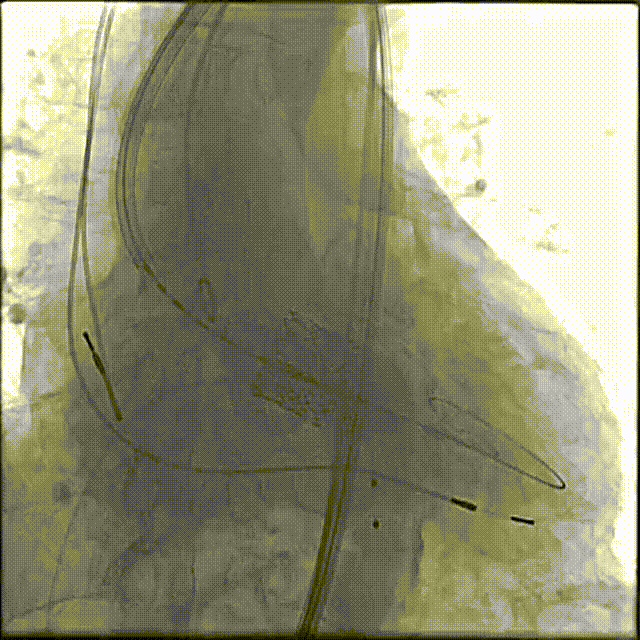

瓣膜释放

最终植入效果